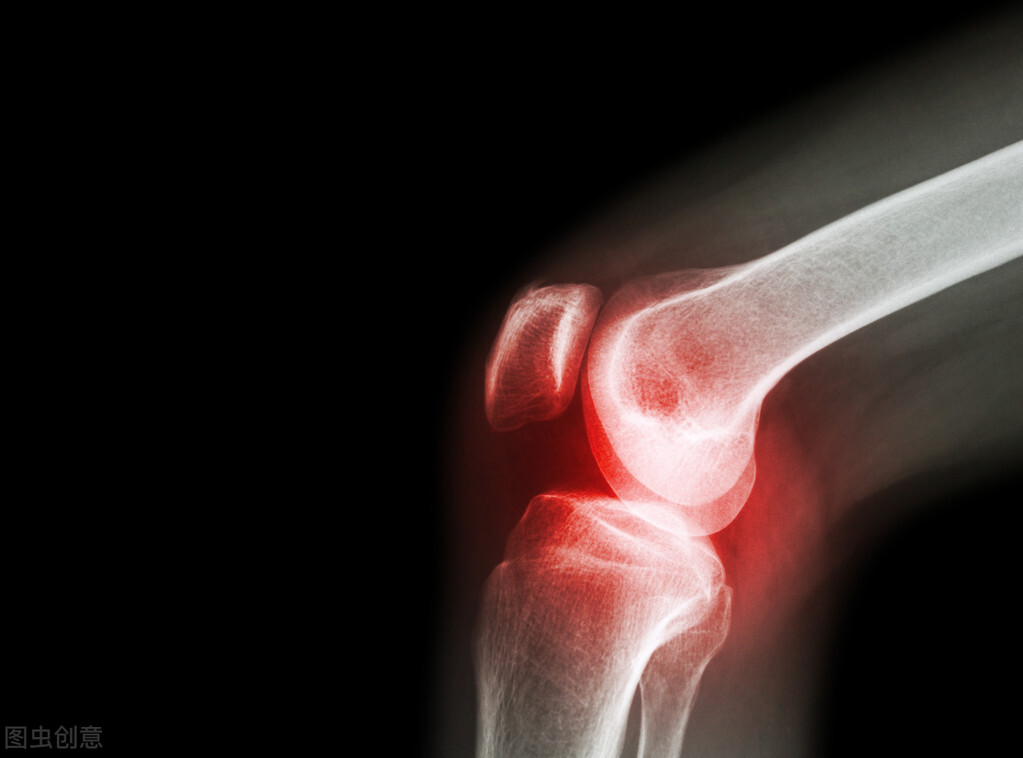

风湿病最常见的症状之一就是疼痛,尤其疼痛发生在晚上,主要是由于夜里血液流速变慢,气血运行不畅,加上夜间气温下降,湿气重,所以会直接导致夜间风湿疼痛。对疼痛的治疗方法有很多,比如用热水泡脚来止痛,用静点的方法,也可以用调节心情的方法。风湿痛为什么在晚上这么严重?接下来,重庆鑫舜风湿医院(原重庆风湿医院)为大家详细介绍。

风湿病最常见的症状之一就是疼痛。风湿病患者会感觉到不同程度的疼痛,而夜间风湿痛则是由于夜间血液以归心,气血循环不畅,加上夜间气温降低,湿气也重,所以风湿病患者会在夜间出现风湿痛。因此,如何缓解夜间风湿疼痛,下面我们就来了解一下晚上风湿疼痛的缓解方法。